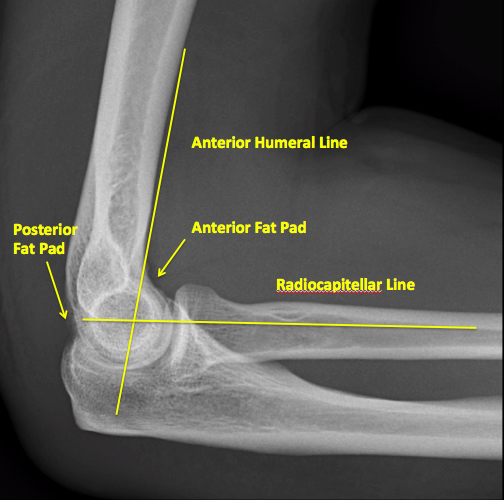

humeral line anterior elbow supracondylar pediatric fractures normal radiology fracture humerus radiopaedia capitellum angle capitulum joint case types injuries occult

elbow ray radial fracture head normal alignment line anterior humeral coreem

elbow forearm normal lateral alignment anterior capitellum radiograph interpreting radiographs fracture supracondylar intersect

elbow line anterior normal radiocapitellar humeral fractures adults lateral radiograph dislocations imaging

humeral radiocapitellar elbow radiographic

elbow humeral fracture supracondylar forearm capitellum radiographs interpreting intersect

elbow xrays humeral radiocapitellar emdocs fracture

elbow xrays anterior humeral radiocapitellar emdocs fracture

humeral lateral elbow rogers

elbow pad fat normal anterior pediatric injuries sign

radiopaedia line humeral anterior radiology

capitellum dislocation elbow pediatric through drawn lateral anterior humeral pass should line

Anterior humeral line. Pediatric humeral fracture. Elbow injuries